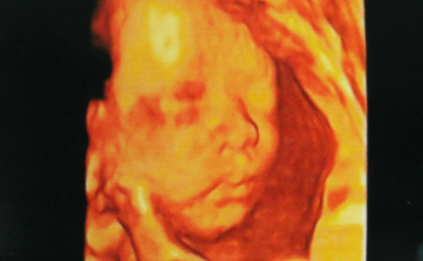

我朋友现在怀孕12周了,最近她跟我说,她发现自己只要把手放在腹部,摸一下肚子,胎儿在子宫内就活动的很厉害,好像是知道妈妈在摸他,但平时不摸的时候,宝宝都是乖乖的在休息,都没怎么动。我感觉好神奇啊,胎儿真的能感觉到妈妈在摸他吗?我朋友这个怀孕周数感觉还早啊,胎儿应该还很小,胎宝宝在子宫内应该还感觉不到吧。